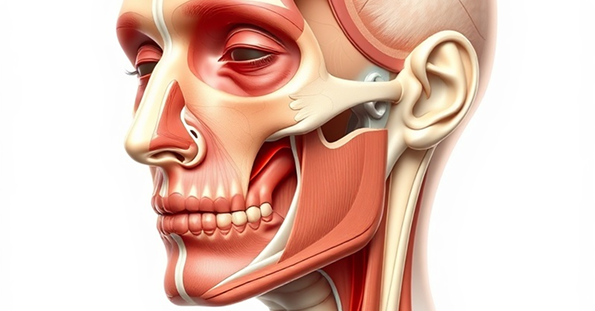

Facial Injury

Recovery

Facial injuries can have profound physical and emotional impacts. We help victims understand their options for treatment and ensure they receive proper legal recourse for their recovery.

Reconstructive Surgery

Expert guidance on restoration options

Legal Support

Comprehensive compensation claims